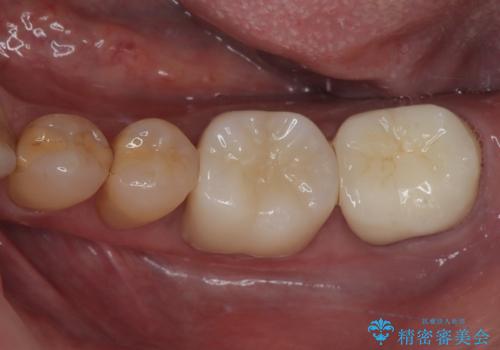

- 21万円(税込) ※3歯費用は治療当時の料金となります

銀歯を気にせずに笑うことができると満足していただきました。